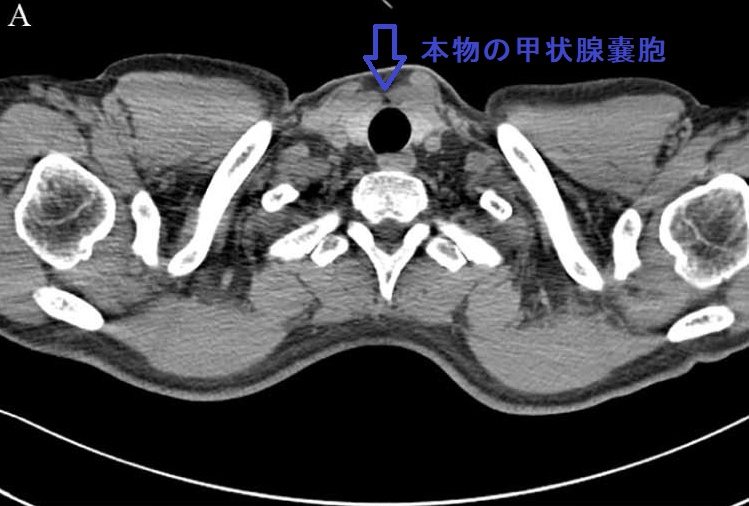

気管に近接する甲状腺嚢胞(のう胞)では、超音波(エコー)検査においてミラーイメージ アーチファクトを生じるケースがあります。過度に収縮して超音波(エコー)を反射しやすくなった気管壁から跳ね返ってきた反射波が、周囲の構造物に当たり、再度気管に向かう2重の反射波が原因(鏡面反射の原理)。この現象により、2重の反射波が時間差を置いて帰ってくるため、気管壁の内側(気管内腔)に同じエコー像が現れます。

もちろん、現実には存在しないアーチファクトなので、頸部CTには写りません。穿刺排液で甲状腺嚢胞(のう胞)が縮小すればミラーイメージも縮小します。

[Radiol Case Rep. 2018 Feb 9;13(2):408-410.]